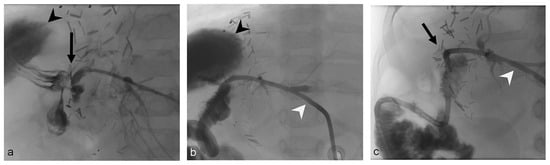

- Uller, W.; Wohlgemuth, W.A.; Hammer, S.; Knoppke, B.; Goessmann, H.; Loss, M.; Schlitt, H.J.; Stroszczynski, C.; Zorger, N.; Heiss, P. Percutaneous treatment of biliary complications in pediatric patients after liver transplantation. Rofo 2014, 186, 1127–1133. [Google Scholar] [CrossRef]